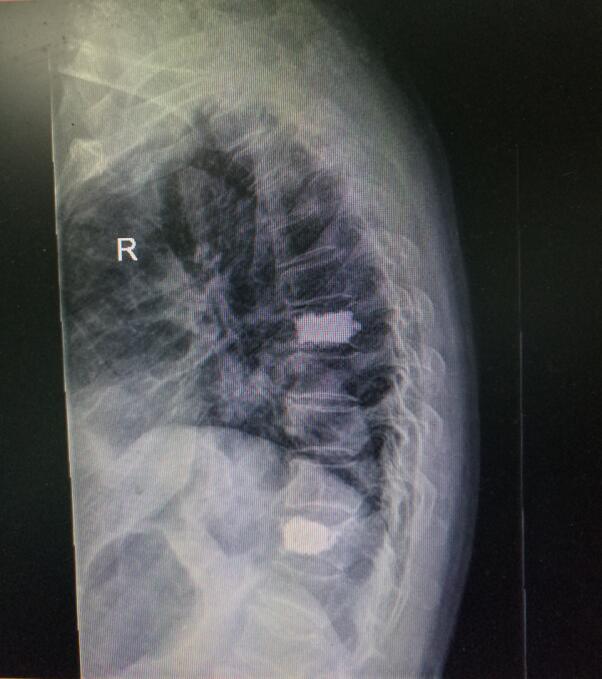

術(shù)前DR(數(shù)字化的x射線)

入院后第四天,由骨傷二科副主任楊陳一、劉永森醫(yī)生、唐國皓醫(yī)生聯(lián)合為患者成功實施了微創(chuàng)下的經(jīng)皮穿刺椎體后凸成形術(shù)。術(shù)后,患者腰背部疼痛逐漸緩解,術(shù)后第二天即下床活動。